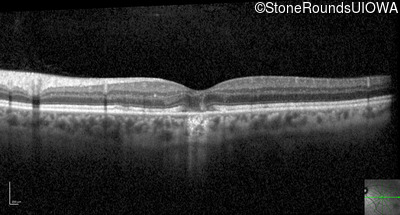

Optical Coherence Tomography - Left - 20/40 -2

Exemplar / OCT Stack

OCT Stack